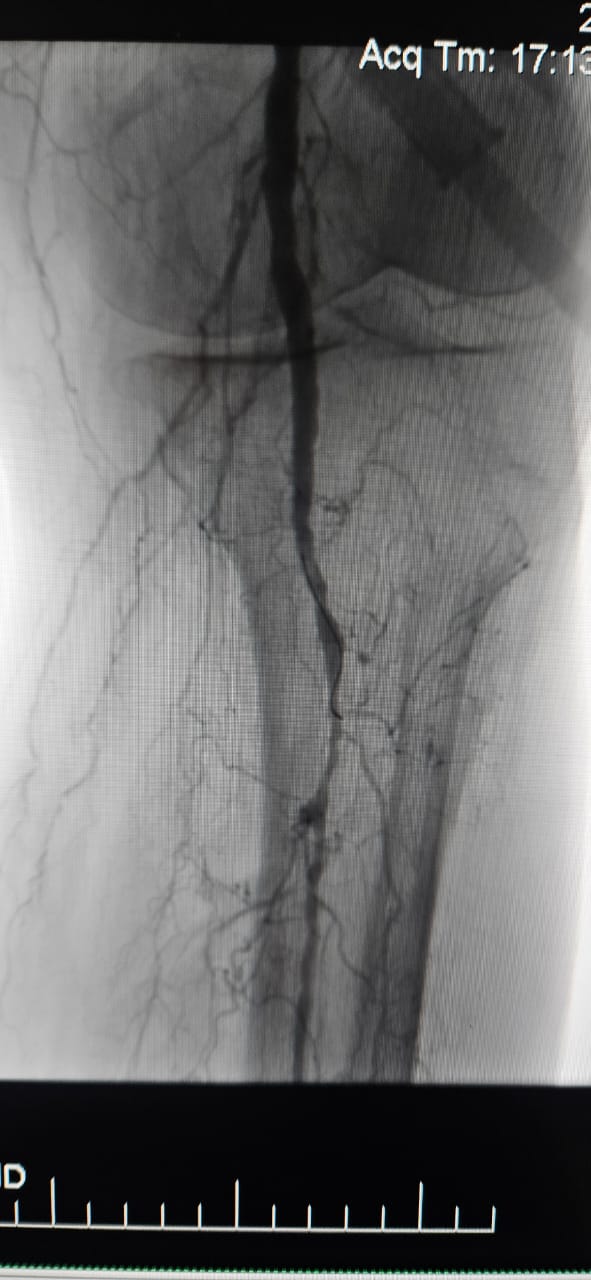

We are pleased to share a successful case from a hospital in Batumi, Georgia, where a 78-year-old female patient with Critical Limb Ischemia (CLI) caused by chronic total occlusion of the lower limb artery showed remarkable clinical improvement following treatment with the ThorCrack Peripheral IVL Balloon Dilatation Catheter System.

This case underscores the clinical value of intravascular lithotripsy (IVL) in the treatment of complex CLI cases with long-segment chronic occlusion—particularly in patients with heavy calcification, where traditional balloons or atherectomy devices may have limited efficacy.

We are proud to see ThorCrack IVL empowering physicians around the world to overcome calcified lesions, restore perfusion, and improve patient outcomes in complex peripheral arterial disease.